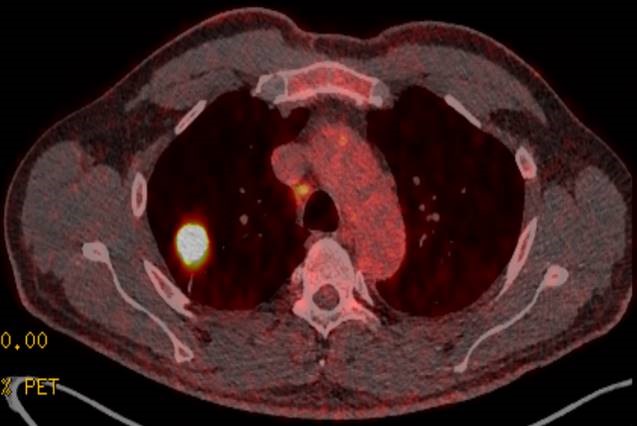

Onkologisches Zentrum